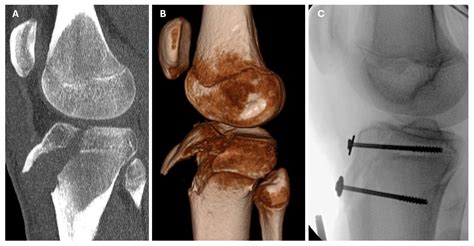

To confirm the diagnosis, medical professionals typically utilize imaging studies. X-rays are the gold standard for visualizing the displaced bone fragment and determining the severity of the fracture. In more complex or comminuted cases, an MRI may be ordered to assess the condition of the surrounding soft tissues, including the patellar tendon and menisci.

However, if the fragment is displaced or if the knee joint is compromised, surgical intervention is mandatory. The surgical procedure typically involves:

• Open Reduction Internal Fixation (ORIF): The surgeon makes an incision to visualize the bone fragment.

• Hardware Placement: The loose piece of bone is secured back to the main tibia using screws, wires, or specialized anchors.